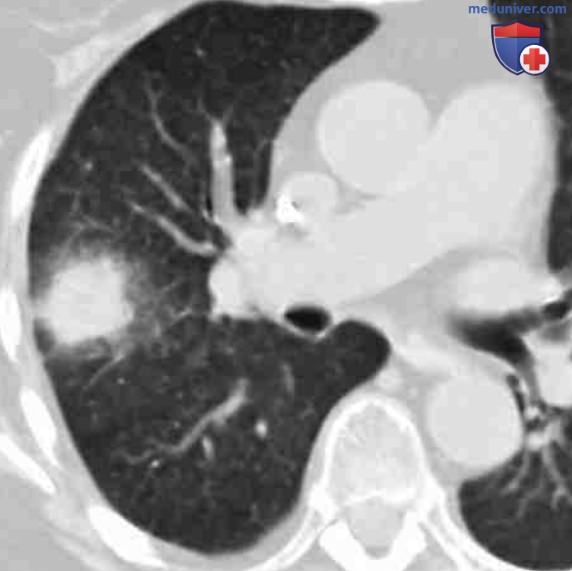

Аспергиллез обычно протекает в ангиоинвазивной форме либо в форме поражения дыхательных путей, манифестируя множественными легочными узелками, нередко окруженными уплотнением типа матового стекла (КТ-симптом гало, см. рис. ниже).

Симптом гало при ангиоинвазивном аспергиллезе. На аксиальной бесконтрастной томограмме в правой верхней доле визуализируется узел, окруженный зоной гало в виде матового стекла. У пациента с фебрильной нейтропенией симптом гало вокруг узловидного образования легкого, скорее всего, является признаком ангиоинвазивного аспергиллеза